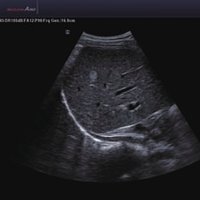

Das Samsung Accuvix A30 ist ein hochwertiges Ultraschallsystem, das mit seiner 3D-Technologie herausragende Ergebnisse ermöglicht. Das Sonographiegerät besitzt 5 Sondenanschlüsse und ist mit 20 unterschiedlichen Schallköpfen kompatibel. Mit dem A30 können Schallköpfe vom Typ Konvex, Mikrokonvex, 3D-Konvex, CW, Phased Array, Linear und Endokavitär verwendet werden. Bei zwei der Sonden handelt es sich um S-VUE Ultraschallsonden, die durch ihre höhere Bandbreite noch feinere Scans erzeugen.

Das Ultraschallsystem hebt sich besonders durch seine 3D-Technologie wie die Face Auto Detection für detaillierte Ultraschallbilder von Föten oder das Volume Shade Imaging, das sich auf die lebensnahe Darstellung von Schattierungen und Hauttönen fokussiert, ab. Mit weiteren wertvollen Technologien wie dem ElastoScan™ werden Tumore schneller erfasst und durch die HD Volumen Bildgebung sowie das DMR+™ eine erstklassige Bildqualität erzielt.